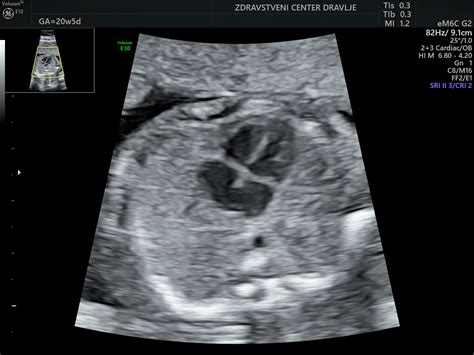

Čeprav je plodovo srce mogoče ultrazvočno pregledati že okoli 16. tedna nosečnosti, se največ pregledov opravi med 20. in 22. tednom, ko je srce veliko približno kot lešnik. Pregled zajema oceno velikosti in lege srca, prikaza votlih ven in pljučnih ven, oceno preddvorov in prekatov ter delovanja zaklopk. Ocenijo se tudi ovalno okence in Botallov vod, ki sta pri plodu odprta, po rojstvu pa se zapreta. Poleg morfologije se ocenjuje tudi funkcija srčne mišice in srčni ritem.

V ZC Dravlje nudijo specializirane ultrazvoke srca pri plodu pri specialistu fetalno ehokardiografije, doc. Samu Veselu, ki lahko odkrije okoli 95 % vseh pomembnih srčnih napak.